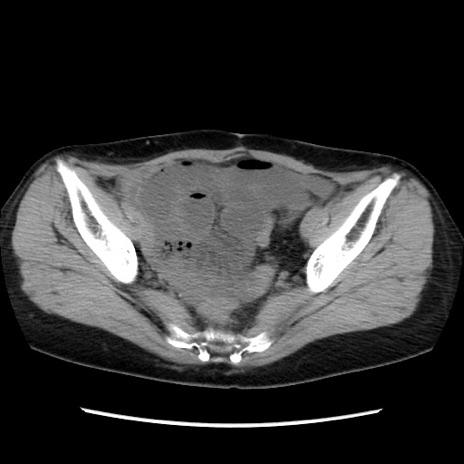

症例32(横断像)

【症例】40歳代 女性

【主訴】上腹部痛、嘔気・嘔吐

【現病歴】約9時間前頃から急に上腹部痛、嘔気、嘔吐が出現。改善しないため救急要請。

【既往歴】子宮頚癌(広汎子宮全摘術、放射線療法)、腸閉塞

【身体所見】腹部:平坦、軟、腸雑音亢進、上腹部を中心に腹部全体に圧痛あり。

【データ】WBC 8400、CRP 0.03